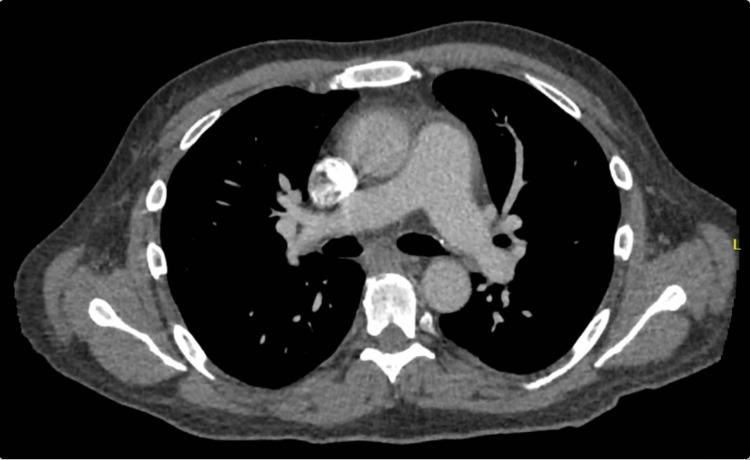

Drug-induced lupus (DIL) usually presents after starting a medication known to induce DIL. However unusual presentations are rare, as such, our patient presented with initial signs and symptoms of pericarditis. Once treated as such, he progressively declined to symptoms of angioedema and worsening cardiopulmonary status. On first admission, the patient presented with chest pain that was worsened by laying down and improved by sitting up. CT Angiography (CTA) showed mild pericardial effusion, and EKG showed diffuse ST elevation, both suggestive of pericarditis, for which the patient was discharged on colchicine. The patient was readmitted one day later with swelling of the neck and tongue. The patient was re-evaluated, tested for autoantibodies, and found a positive antinuclear antibody (ANA) suggesting a diagnosis of lupus, most likely due to hydralazine. We report a rare presentation of drug-induced lupus initially presenting with pericarditis which evolved into worsening angioedema which has not been reported in the literature thus far. Pericarditis and angioedema may be the initial presentation for a patient with drug-induced lupus. Antinuclear and anti-histone antibodies are highly sensitive and specific respectfully for drug-induced lupus. Early diagnosis and time-appropriate discontinuation of the offending agent for patients can be life-saving.

药物性狼疮(DIL)通常在开始使用已知可诱发DIL的药物后出现。然而,不寻常的表现很少见,因此,我们的患者最初表现为心包炎的体征和症状。在按此进行治疗后,他的病情逐渐发展为血管性水肿症状,心肺状况也不断恶化。首次入院时,患者出现胸痛,躺下时加重,坐起时缓解。CT血管造影(CTA)显示轻度心包积液,心电图显示广泛ST段抬高,两者均提示心包炎,患者因此出院时服用秋水仙碱。一天后患者再次入院,出现颈部和舌头肿胀。对患者进行了重新评估,检测了自身抗体,发现抗核抗体(ANA)呈阳性,提示狼疮诊断,很可能是由肼屈嗪引起的。我们报告了一例罕见的药物性狼疮病例,最初表现为心包炎,随后发展为不断加重的血管性水肿,迄今为止文献中尚未有过此类报道。心包炎和血管性水肿可能是药物性狼疮患者的初始表现。抗核抗体和抗组蛋白抗体分别对药物性狼疮具有高度敏感性和特异性。对患者进行早期诊断并及时停用致病药物可能会挽救生命。